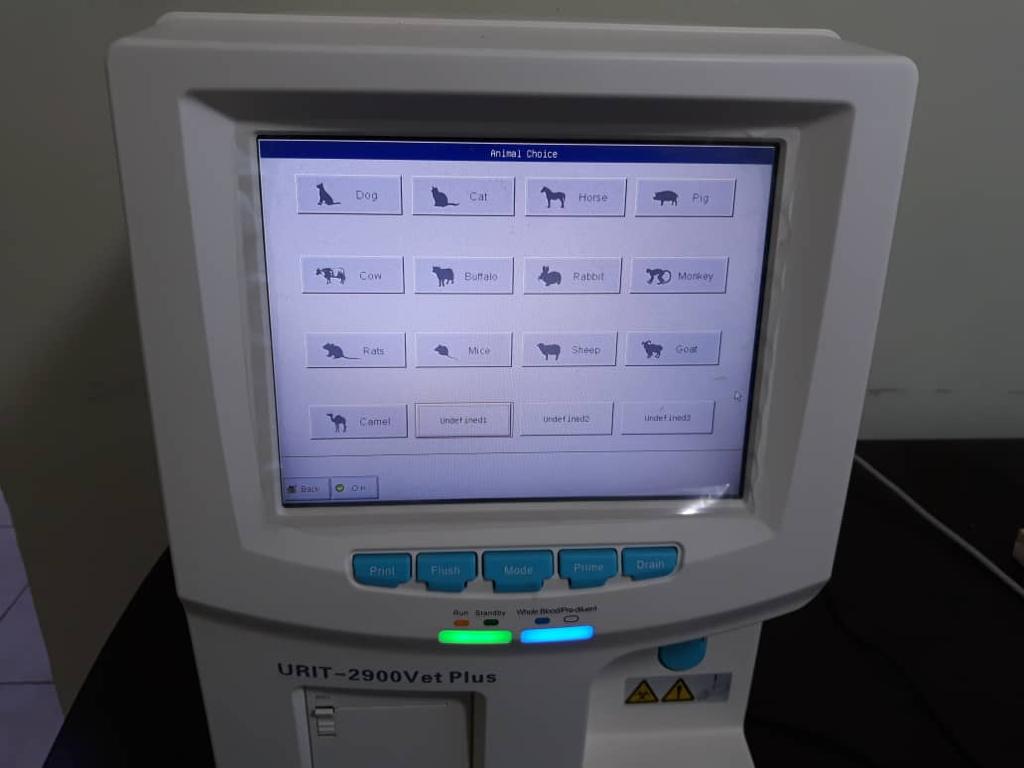

علاوه بر سگ و گربه، حیوانات خانگی خاص مانند خرگوش، همستر، پرندگان زینتی و خزندگان نیز توسط دامپزشکان متخصص ویزیت میشوند.